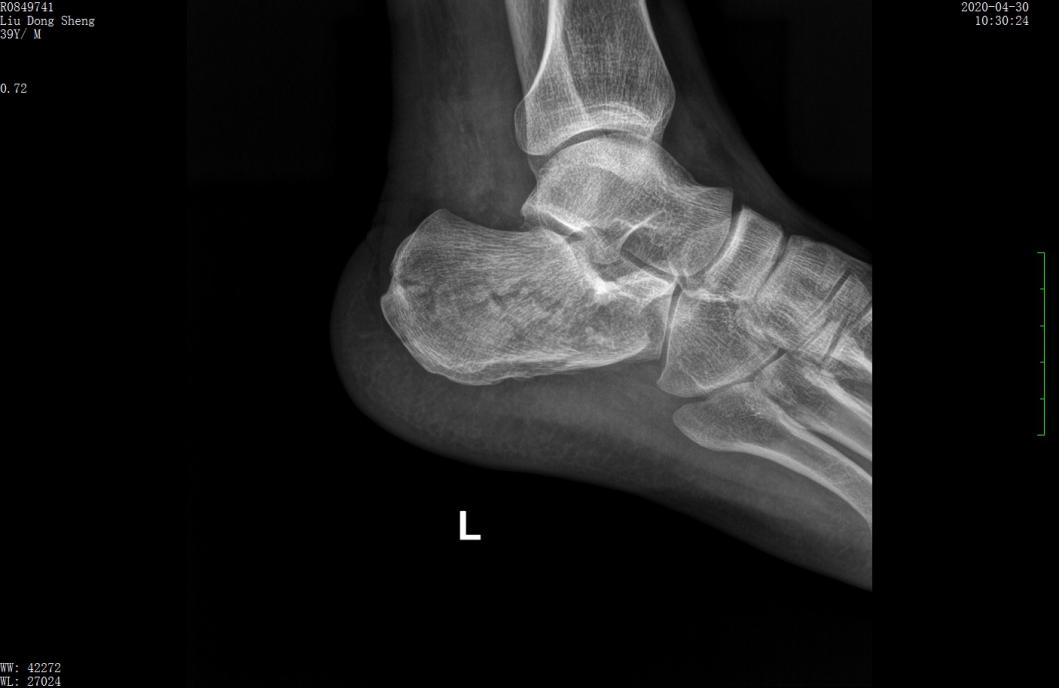

案例1影像

术前X线示跟骨高度丢失,关节面塌陷